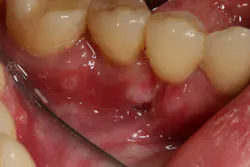

- 10% to 15% of canker sores are major aphthous ulcers, usually larger than 10 mm in diameter, and can occur on both keratinized and nonkeratinized mucosa. These lesions can last two to eight weeks and may cause scarring in some cases (figure 2).

Figure 2: Major aphthous ulcer